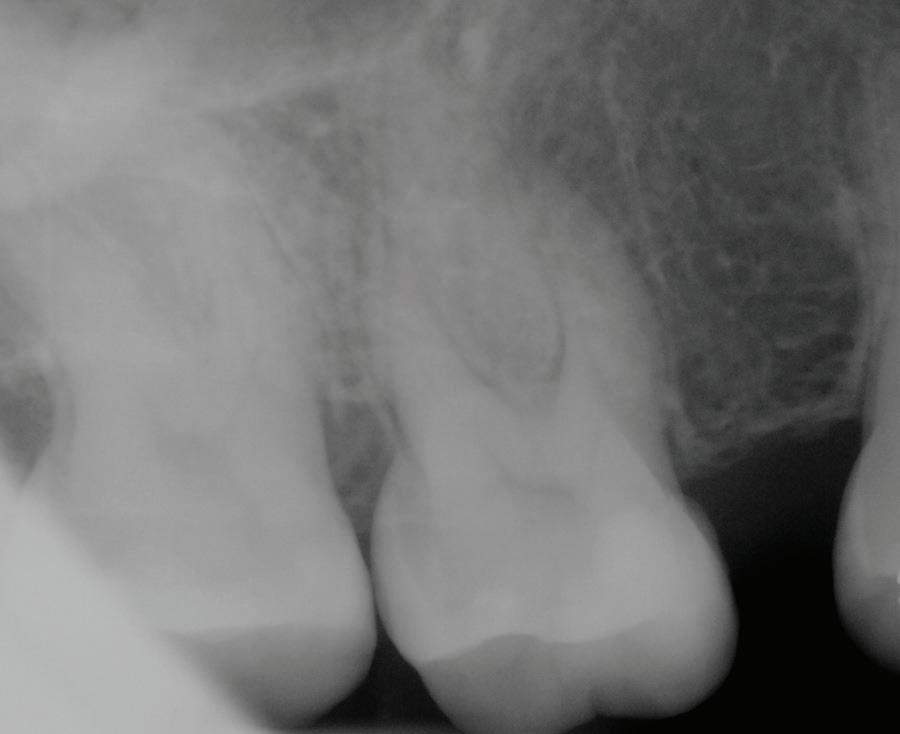

Fig 1. Proximity of root apices to vital structures. A. The periapical radiograph indicates that the apices of the mandibular right second molar and second premolar are in proximity to the inferior alveolar and mental nerves. B. A coronal CBCT image more clearly demonstrates the proximity of the molar apex to the inferior alveolar nerve. C. A coronal CBCT image more clearly demonstrates the proximity of the premolar apex to the mental nerve.

The inferior alveolar canal courses closely beneath the apices of mandibular molars, particularly second molars. Studies have shown that in more than 25% to 30% of patients, the inferior alveolar canal lies within 1 mm of the root apices of second molars; the prevalence is even higher in female and older patients due to reduced bone volume (Fig 1).8

Proper diagnosis is essential to identifying cases at risk of extrusion. Conventional periapical radiography remains a fundamental diagnostic tool in endodontics, offering high-resolution, real-time imaging at low radiation exposure and minimal cost. However, the 2-dimensional (2D) nature of periapical radiographs presents inherent limitations when complex root anatomy is evaluated, especially in the apical third.

One of the most significant shortcomings of periapical radiography is its inability to provide information in the buccolingual dimension. This makes it difficult to detect resorptive lesions (internal or external) located on the buccal or lingual surfaces; fenestrations or dehiscences in the cortical plate; split canals, C-shaped canals, or isthmuses hidden in a single projection; and superimposed anatomical structures, including the zygomatic arch over maxillary molars or mental foramen overlapping premolar apices.

To improve diagnostic accuracy, clinicians are encouraged to take multiple angulated views. However, even with angulated views, the 2D limitation persists, and structures with significant buccolingual spread or overlap may still be misinterpreted. In cases in which a patient’s symptoms persist despite normal

radiographic findings, or an apical resorption, a fenestration, or an anatomical anomaly is suspected, reliance on periapical radiographs alone may result in missed diagnoses or mismanagement (Fig 4).

Additionally, periapical radiographs may underestimate the extent of periapical bone loss or resorption if confined to the cortical plate or masked by trabecular density. For instance, studies have shown that periapical radiolucencies must involve at least 30% mineral loss in the bone to be radiographically visible.24,25